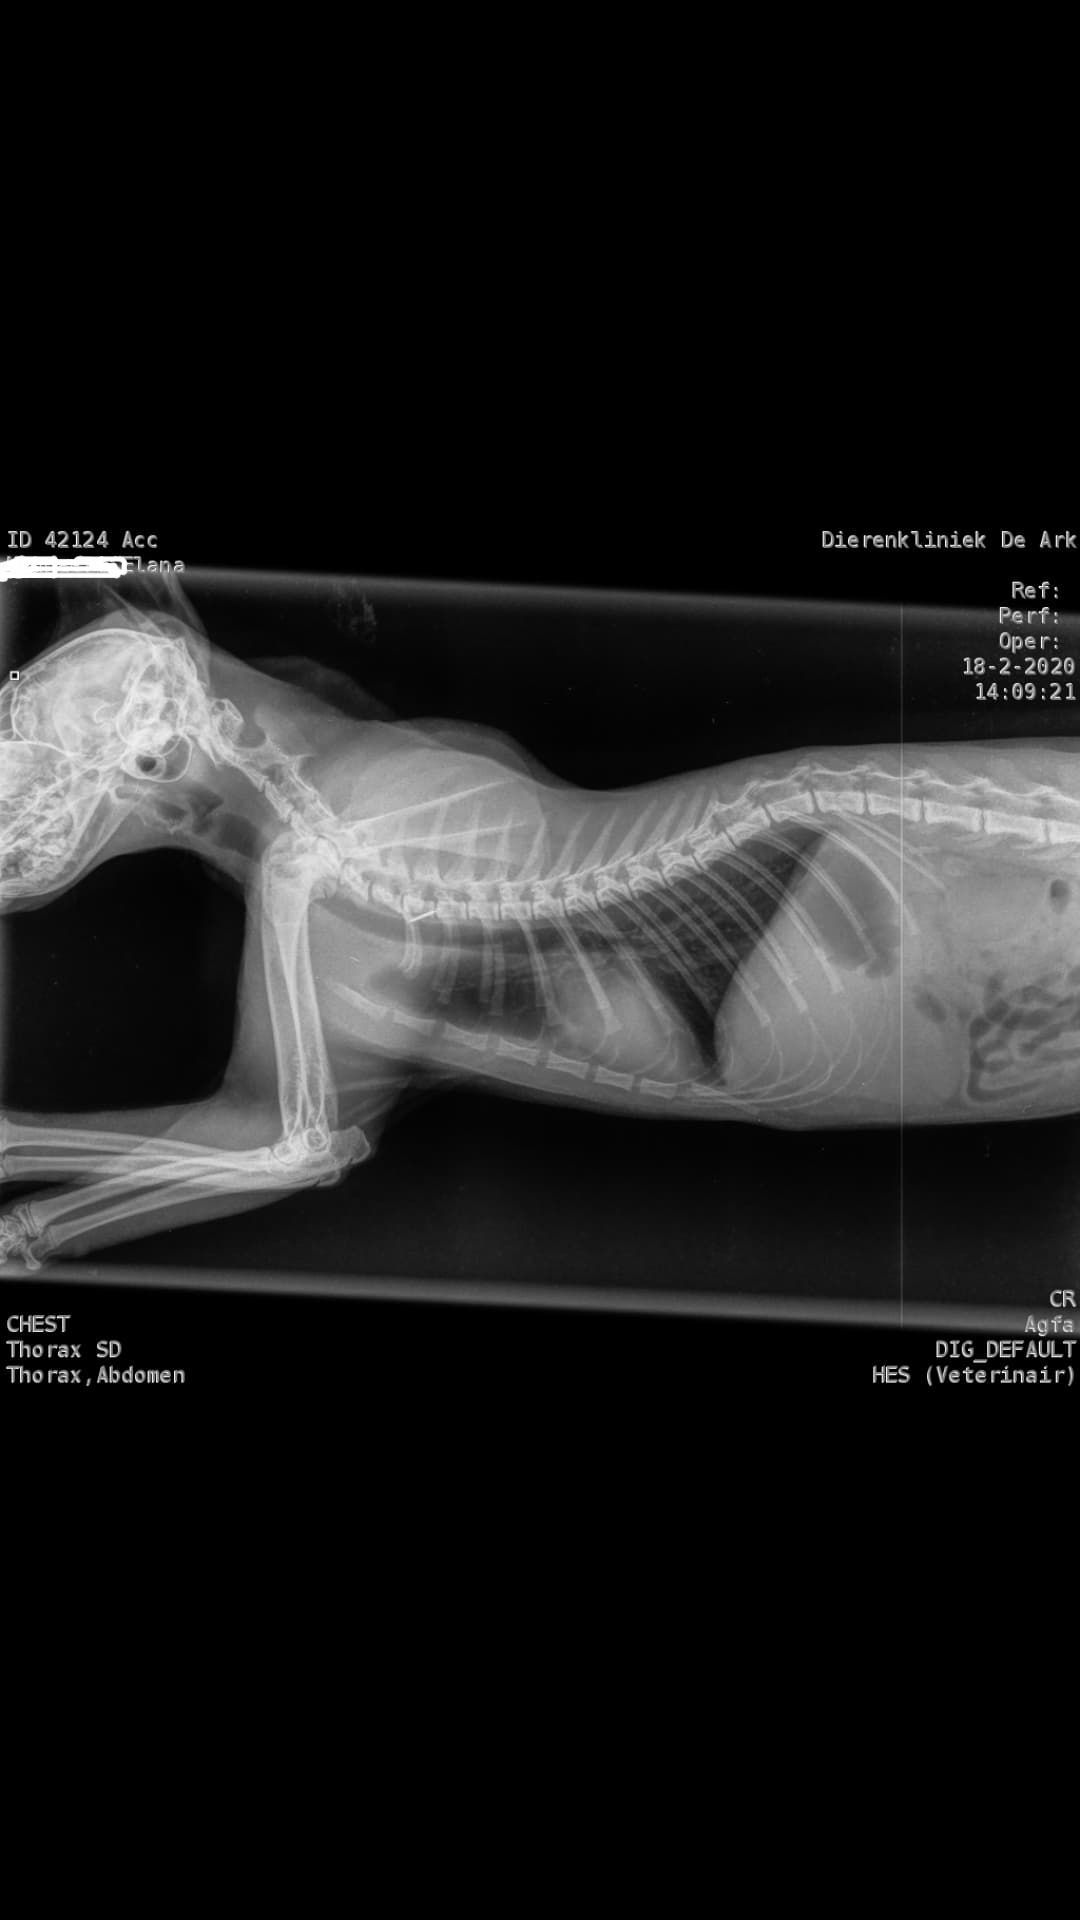

39 graden gemeten bij de dierenarts. De bloedonderzoeken laten al zien dat de waardes enorm veranderd zijn en reden zijn tot het hebben van grote zorgen. Elana is verder volledig nagekeken. Een eventueel ongeluk is uitgesloten d.m.v. rontgenfoto's.  Haar A/G waardes zijn nu gezakt naar 0,57 dit was op dag 82 van de behandeling maar liefst 1,13

3,200 kg , echo en nieuw bloedonderzoek gedaan wat perfect ging door middel van gapabetine

Voor de garanties en om recht te hebben op medicatie bij herval eist Mutian diverse onderzoeken en controle momenten. Dit zijn bloedonderzoeken maar ook zoals hieronder te zien is echo's. Elana is volledig gecontroleerd op afwijkingen, gelukkig waren de echo's goed.